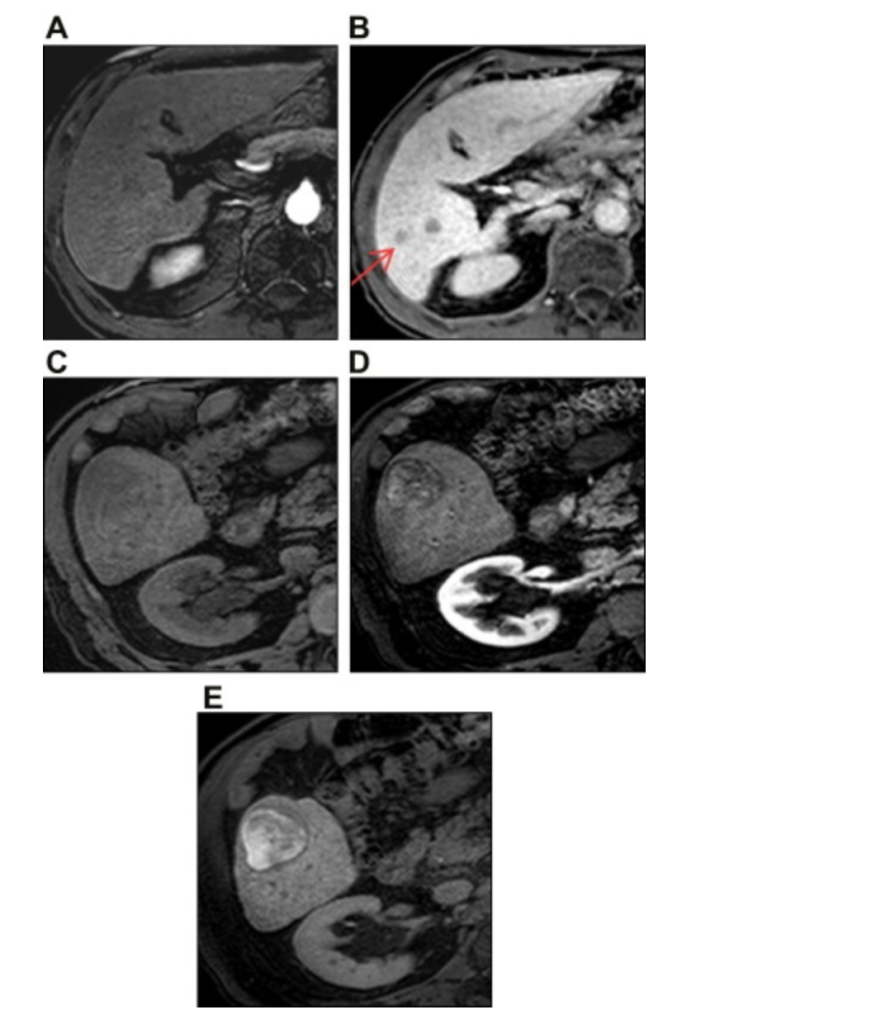

МР-изображения печени с контрастированием GD-EOB-DTPA у двух пациентов с гепатоцеллюлярной карциномой (ГЦК).

(A) У первого пациента очаг не определяется в артериальную фазу при МРТ с GD-EOB-DTPA из-за отсутствия гиперваскуляризации в небольшой ГЦК.

(B) Две небольшие ГЦК (стрелка) визуализируются как гипоинтенсивные узлы в правой доле печени в гепатобилиарную фазу.

(C) У другого пациента ГЦК правой доли печени выглядит изоинтенсивной по отношению к печени на неусиленном Т1-взвешенном изображении.

(D) Прогрессирующая ГЦК гиперваскулярна в артериальную фазу.

(E) Опухоль становится гиперинтенсивной в гепатобилиарную фазу при МРТ с контрастированием GD-EOB-DTPA.